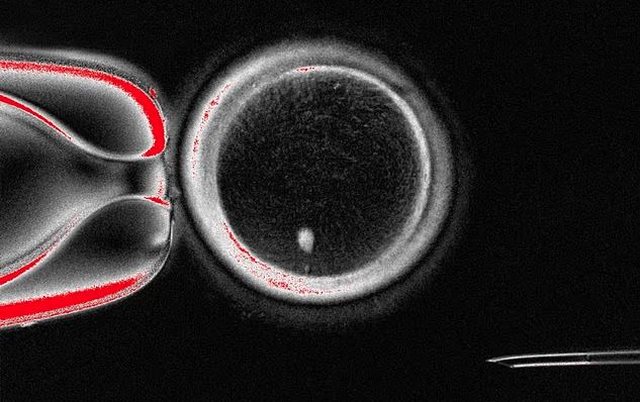

Në kuadër të studimit, shkencëtarët krijuan 82 vezë artificiale, nga të cilat rreth 9% u zhvilluan deri në fazën e blastocistit, një fazë e hershme e embrionit. Edhe pse shumica nuk arritën të zhvillohen më tej dhe disa shfaqën anomali kromozomale, ekspertët e cilësuan këtë si një “provë emocionuese të konceptit”.